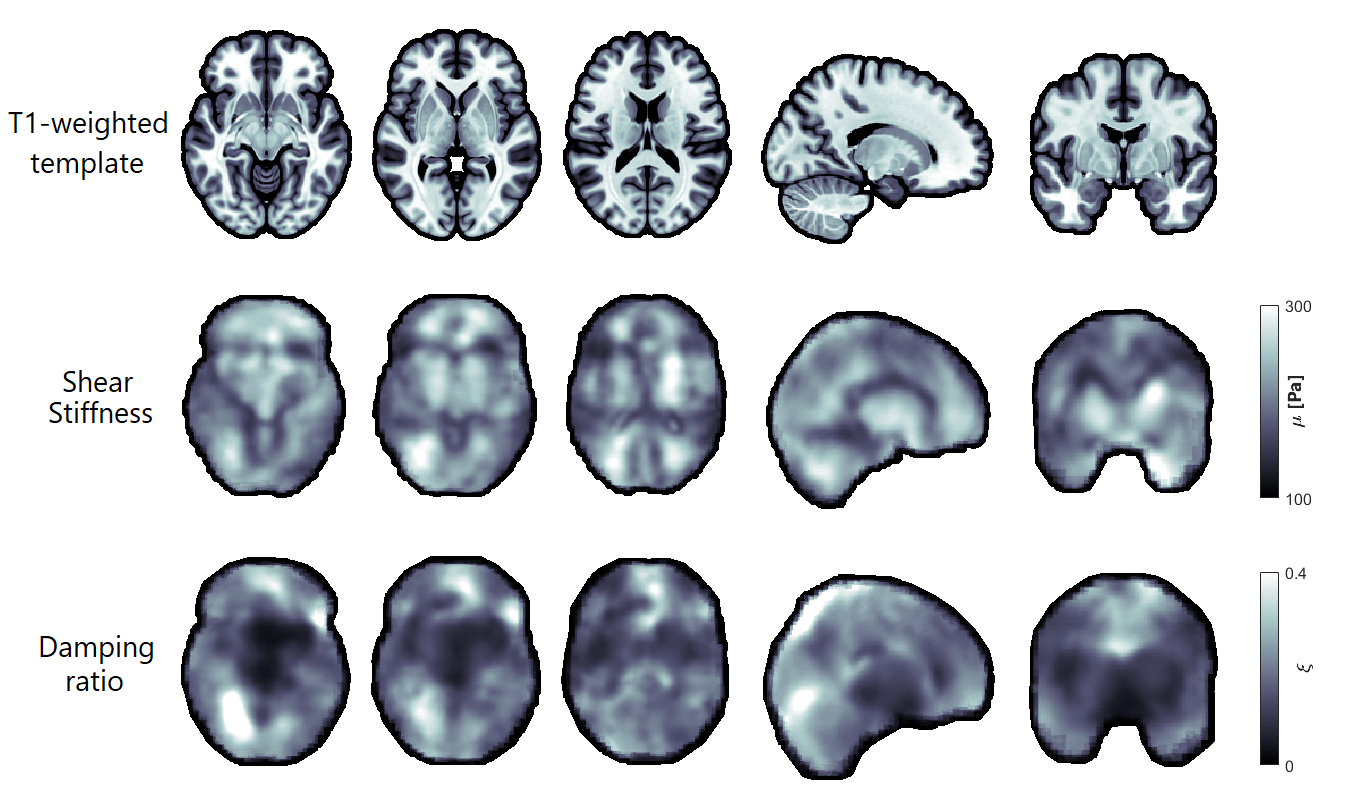

Figure 1 shows representative axial slices for each stiffness parameter along with repeat scans that have been registered to the original scans. Figure 2 shows the mean over all subjects and repeats for each stiffness parameter, where the distributions have been registered to the MNI-ICBM2009c brain atlas7. Table 1 shows the mean and standard deviation for each stiffness parameter, separated for the grey and white matter and the repeat scans. A paired t-test shows that the gray and white matter distributions are not significantly different for any stiffness parameter. Figure 3 shows an example plot of a Bland-Altman analysis for one subject. Figure 4 shows a summarized repeatability analysis for each subject and stiffness parameter, separated for the grey and white matter. Each error bar represents a summarized Bland-Altman plot where the dot represents the mean of the two scans and the whiskers represent the limits of agreements.

The mean distributions in Figure 1 shows a lot of structural features of the brain. In particular, the shear stiffness shows good agreement with the T1-weighted templates in each of the shown slices. This is also reflected in Figure 2, where again many features of the brain can be seen. Additionally, the repeat scans show very good agreement with the original scans, adding confidence to the repeatability. In some places along the periphery of the brain, bright areas of large values can be seen. Such “hotspots” are likely artifacts that arise due to the large quantity of cerebrospinal fluid (CSF) that exists along the boundary of the brain which moves significantly faster than the surrounding tissue, giving artifact-like values during the acquisition. Work is ongoing to mask such voxels but is not yet implemented for these results. The stiffness parameter distributions show very similar values in both scans for all parameters, as shown in Table 1. The grey and white matter also exhibit similar stiffness parameter, with white matter being only slightly stiffer on average. This is again reflected in Figure 3, where the same pattern is observed in all subjects. The comparative length of the two whiskers in an error bar captures the difference between the two scans. Some slight bias can be seen in some measurements, although this is likely predominantly an effect of the previously described hotspots as they appear sporadically between repeat scans. The non-uniqueness of the viscoelastic solution at low frequencies renders only comparative values of interest in this analysis. Future work aims to perform a regional analysis, as well as to integrate a poroelastic brain model in the NLI reconstruction scheme, which is shown to produce unique solutions even at low frequencies6.

Representative axial slices of the shear stiffness and the damping ratio for one subject along with repeat scans that have been registered to the first scan.

Mean values over all subjects and repeats for the shear stiffness and damping ratio for three axial slices, one sagittal and one coronal. Each distribution has been registered to the MNI-ICBM2009c brain atlas.